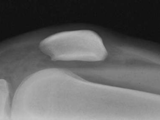

Multiple hereditary exostoses-knee

Multiple hereditary exostoses-knee